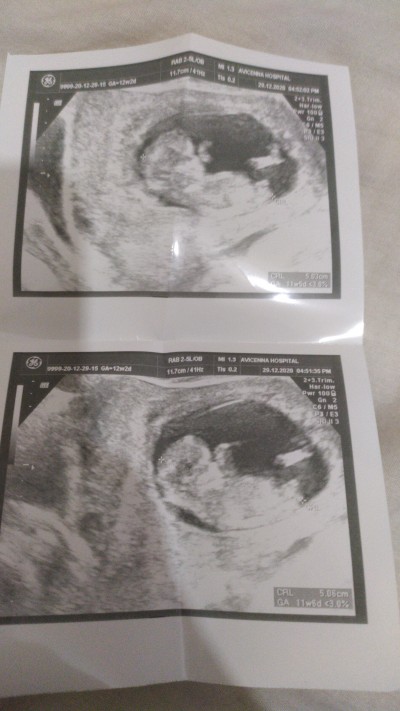

12+2 olduk fakat doktor tahminde bile bulunmadı sizce tahminler nedir

image